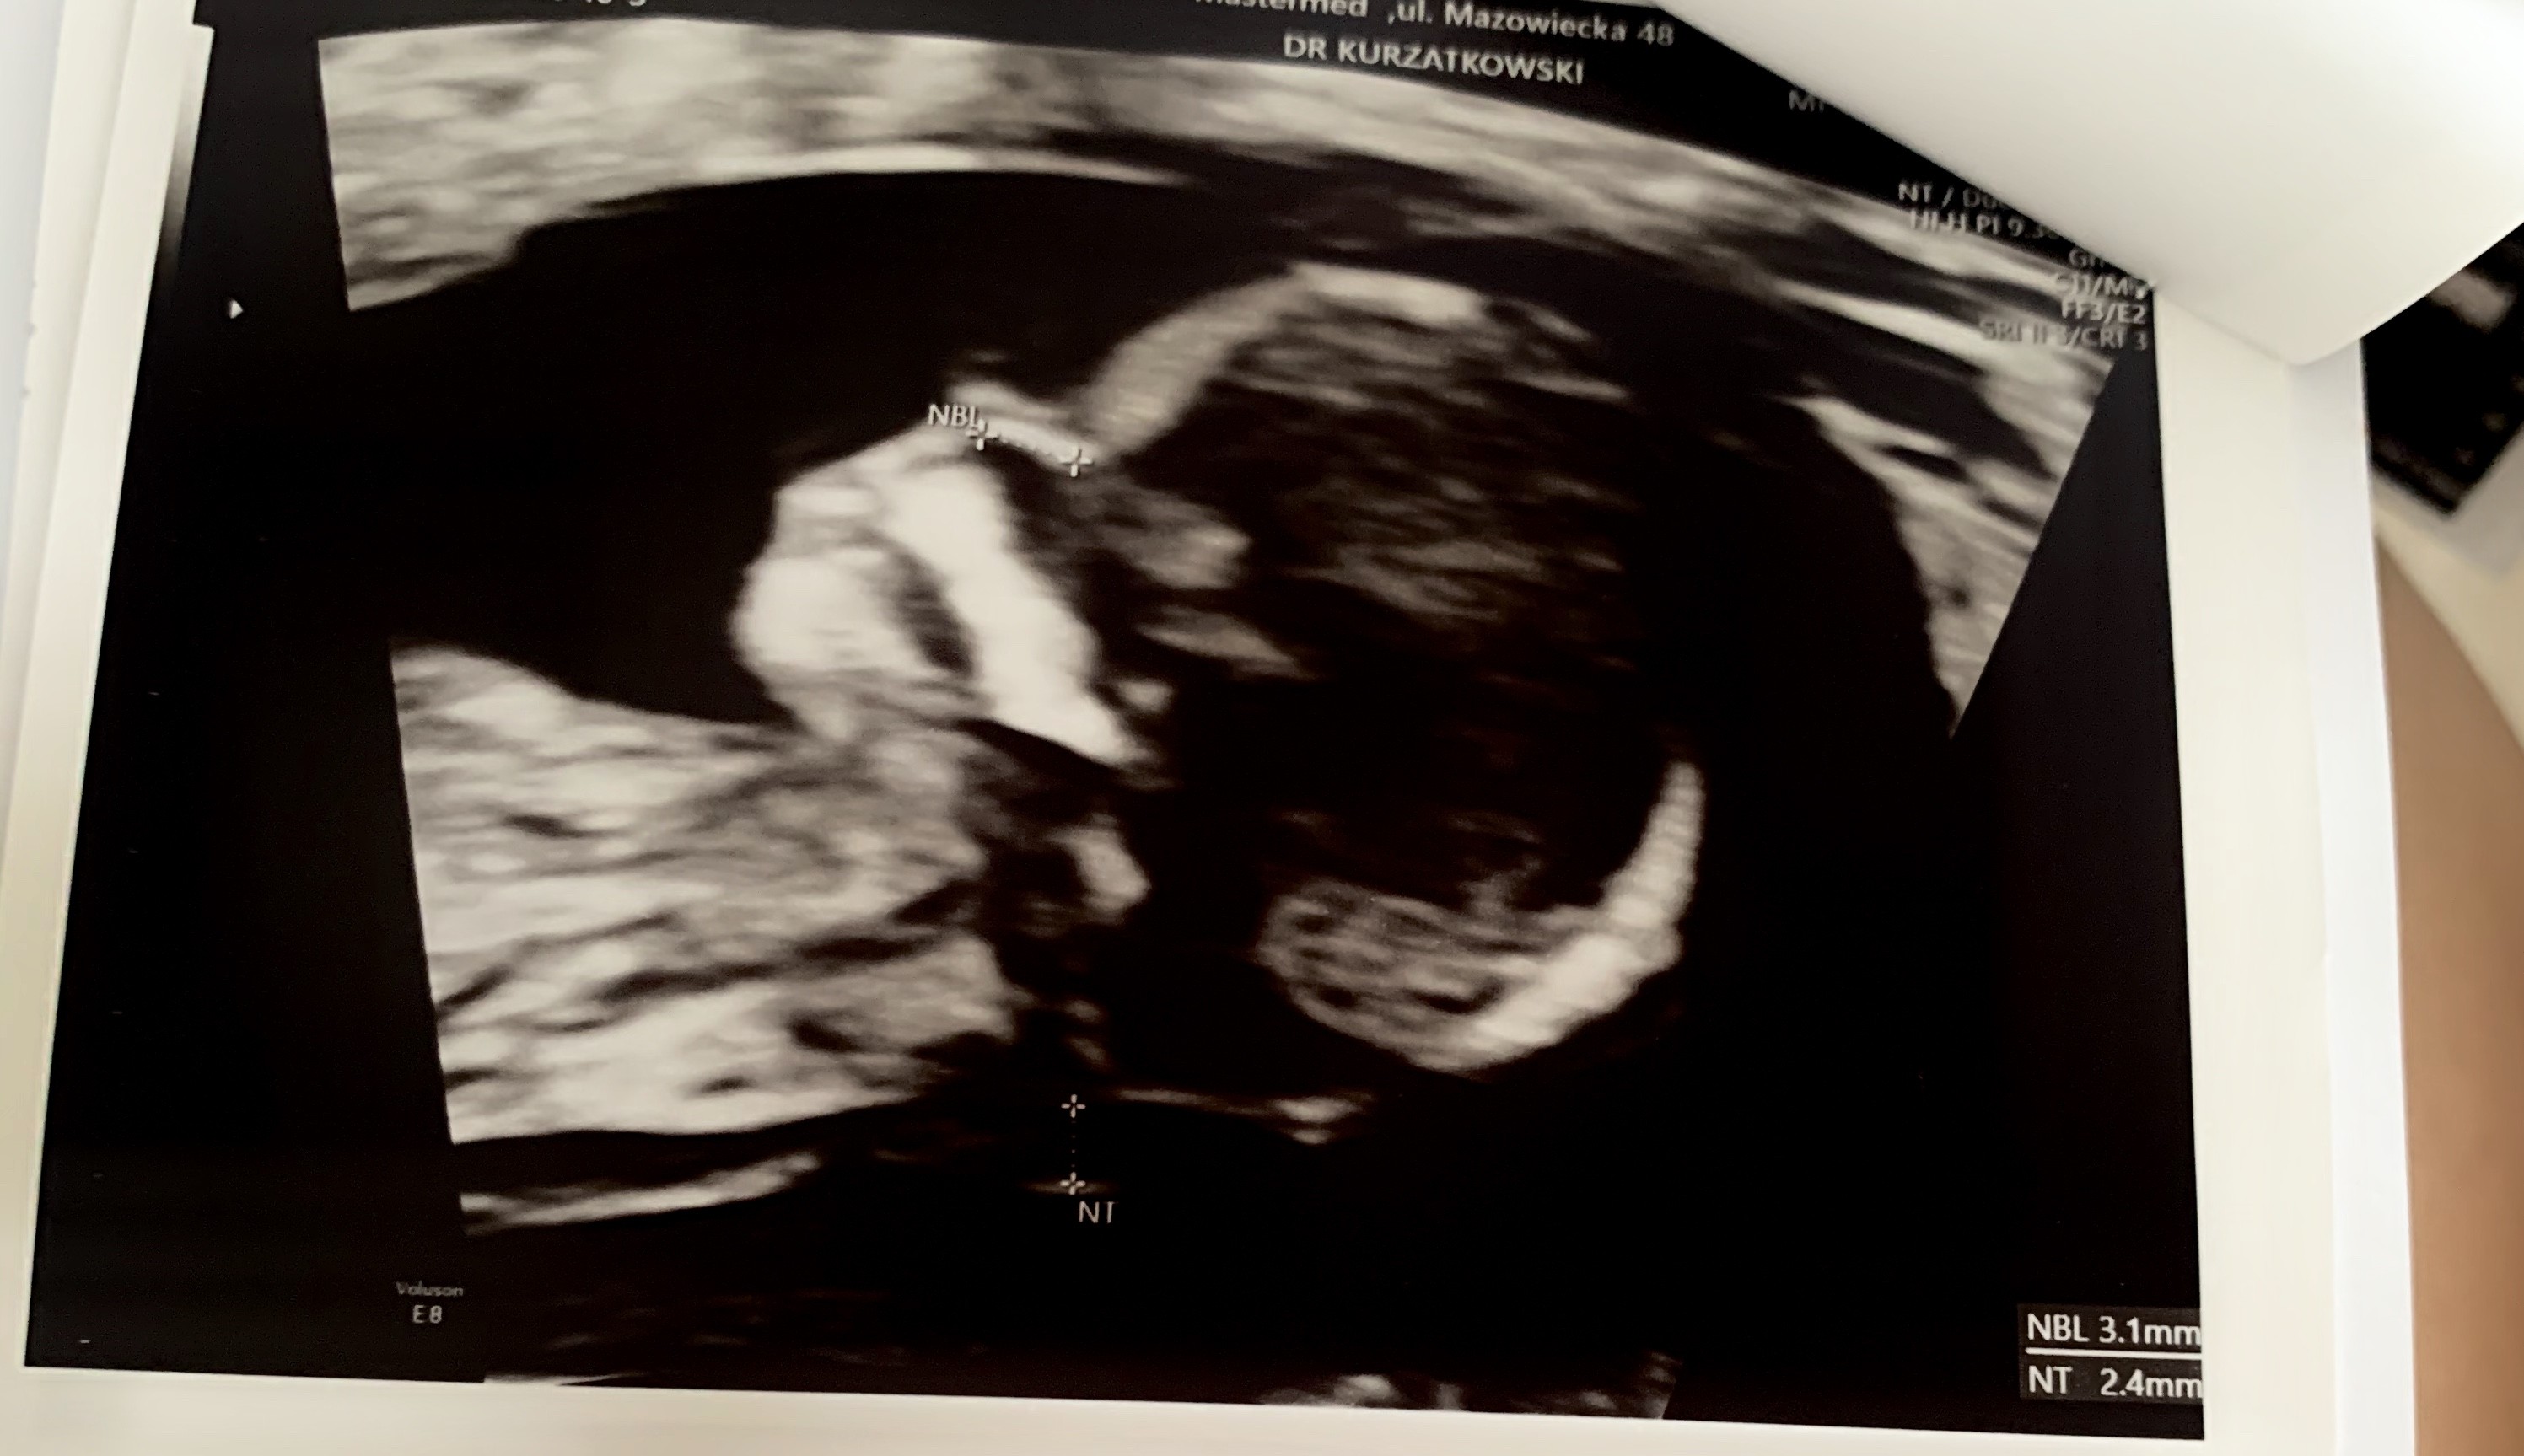

Ja już tez po , jestem zadowolona, wszystko szybko i sprawnie. Na początku USG, wiercioch nie chciał współpracować ale widać doświadczony dr sobie szybko poradził z pomiarami. Dzidziuś całe 7cm długości . Reszta pomiarów zgodna z terminem porodu . Po Usg pobrali krew na test Pappa. Badania miałam bezpłatne ze względu na wiek (35lat), trochę się obawiałam jak to będzie , ja taka”stara” .... ale dziś byłam tam najmłodsza